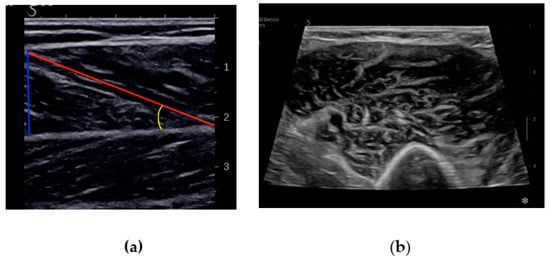

MUS provides an easy-to-use, noninvasive and point-of-care tool for assessing sarcopenia with the advantage of multiple sequential assessments. It allows one to estimate the muscle mass and to evaluate the distribution of adipose and fibrous tissue within skeletal muscle. The European Geriatric Medicine Society (EuGMS) sarcopenia group recently proposed a consensus protocol on the ultrasound evaluation of muscle mass, which involves the measurement of MT, CSA, FL, PA and EI [] (Figure 2). In particular, MUS can provide a detailed evaluation of the quantitative and qualitative parameters of specific anatomical sites.

Figure 2.

(a) A longitudinal US scan of the gastrocnemius muscle showing muscle thickness (blue line), fascicle length (red line) and pennation angle (yellow line); (b) a transverse US scan of biceps muscle showing cross-sectional area.